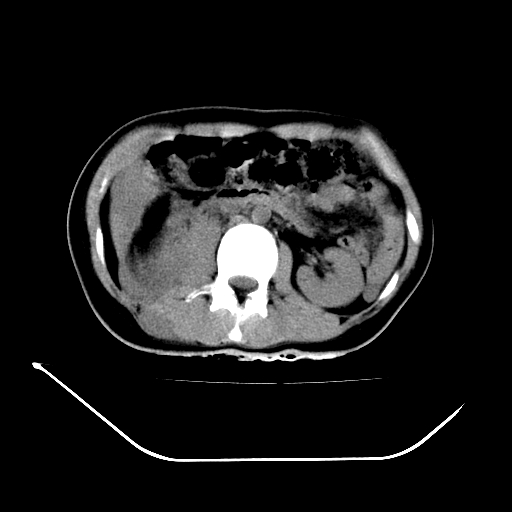

以下是引用liuyue在2008-7-19 13:02:00的发言:[br]1.肝右叶后下段及右肾挫裂伤伴腹腔积血。[br]2.右侧多发性肋骨骨折、横突骨折、右髂骨骨折伴周围软组织挫伤。[br]3.右侧腰大肌肿胀,并可见低密度影,如为气体,则肠道挫裂伤待除外。

以下是引用zhengfaming在2008-7-19 14:42:00的发言:[br]1.肝右叶后下段及右肾挫裂伤伴腹腔积血。脾脏挫裂伤待排[br]2.右侧多发性肋骨骨折、横突骨折、右髂骨骨折伴周围软组织挫伤。[br]3.右侧腰大肌肿胀,并可见低密度影,如为气体,则肠道挫裂伤待除外

以下是引用道哥在2008-7-19 16:52:00的发言:[br]肝右叶后下段及右肾挫裂伤、脾破裂伴腹腔积血。[br]2.双侧多发性肋骨骨折、横突骨折、右髂骨骨折伴周围软组织挫伤。[br]3.右侧腰大肌肿胀,并可见低密度影,如为气体,则肠道挫裂伤待除外。